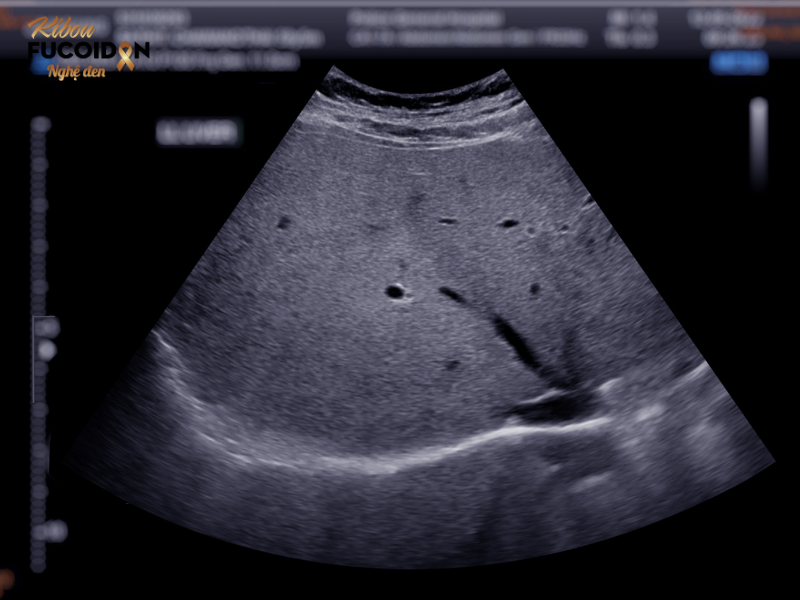

Tầm soát: Siêu âm gan + Xét nghiệm AFP (đặc biệt nam giới >40 tuổi).